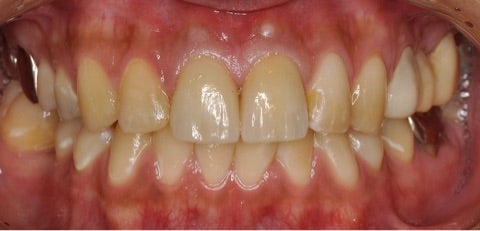

診査診断後、患者様と十分にカウンセリングを行い、無痛治療での全顎的治療を開始しました。

奥歯は重度の虫歯で抜歯をしなければいけない部位があり、目立たない部位には健康保険を使用し、銀歯での処置をしています。

ダメージの大きい前歯(一番前の2本)に対しては、周りの歯の色に特徴があることからジルコニアセラミッククラウン・プレミアム ¥220,000-/本

を使用し、歯科技工士立会いの下、周りの歯と調和するように治療、作成を行いました。